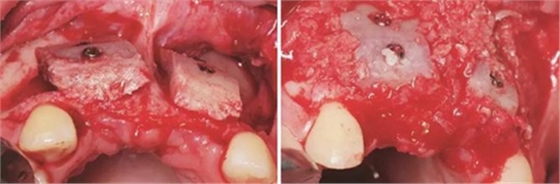

圖7 受植區(qū)固定髂骨骨塊 圖8 自體骨屑與人工骨粉混合后充填植骨間隙

圖9 嚴(yán)密縫合創(chuàng)口 圖10 植骨后拆線

(2)2014年7月:行髂骨取骨,水平向Onlay植骨全麻下患者取平臥位,將取骨側(cè)的髂嵴墊高。標(biāo)記髂前上嵴,在髂嵴下方2cm處做切口,將局部的皮膚緊繃,使其位于髂嵴上方,切口方向同髂嵴,切開髂嵴中線外緣腱膜,剝離骨面附著肌肉至暴露足

夠骨面,使用骨鑿等取骨器械制取骨塊,填塞明膠海綿,分層縫合??趦?nèi)切開植骨區(qū)粘膜,翻瓣,充分暴露待植骨區(qū),用裂鉆在受骨區(qū)骨面預(yù)備若干滋養(yǎng)孔,修整骨塊,以器械夾持骨塊置于手術(shù)受植骨區(qū)并緊貼骨床,使用鈦釘牢固地固定骨塊,植骨塊間的間隙用自體骨屑及少量骨粉(Geistlich Bio-Oss,瑞士)混合后充填,充分減張后嚴(yán)密縫合創(chuàng)口。告醫(yī)囑,囑患者術(shù)后幾天盡量臥床休息,十天后拆線。拍攝CBCT示:牙槽嵴寬度擴(kuò)增明顯:12位點(diǎn)擴(kuò)增至7.4mm-12.4mm,22位點(diǎn)擴(kuò)增至7.4mm-12.2mm。